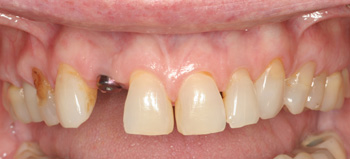

Clinical Cases